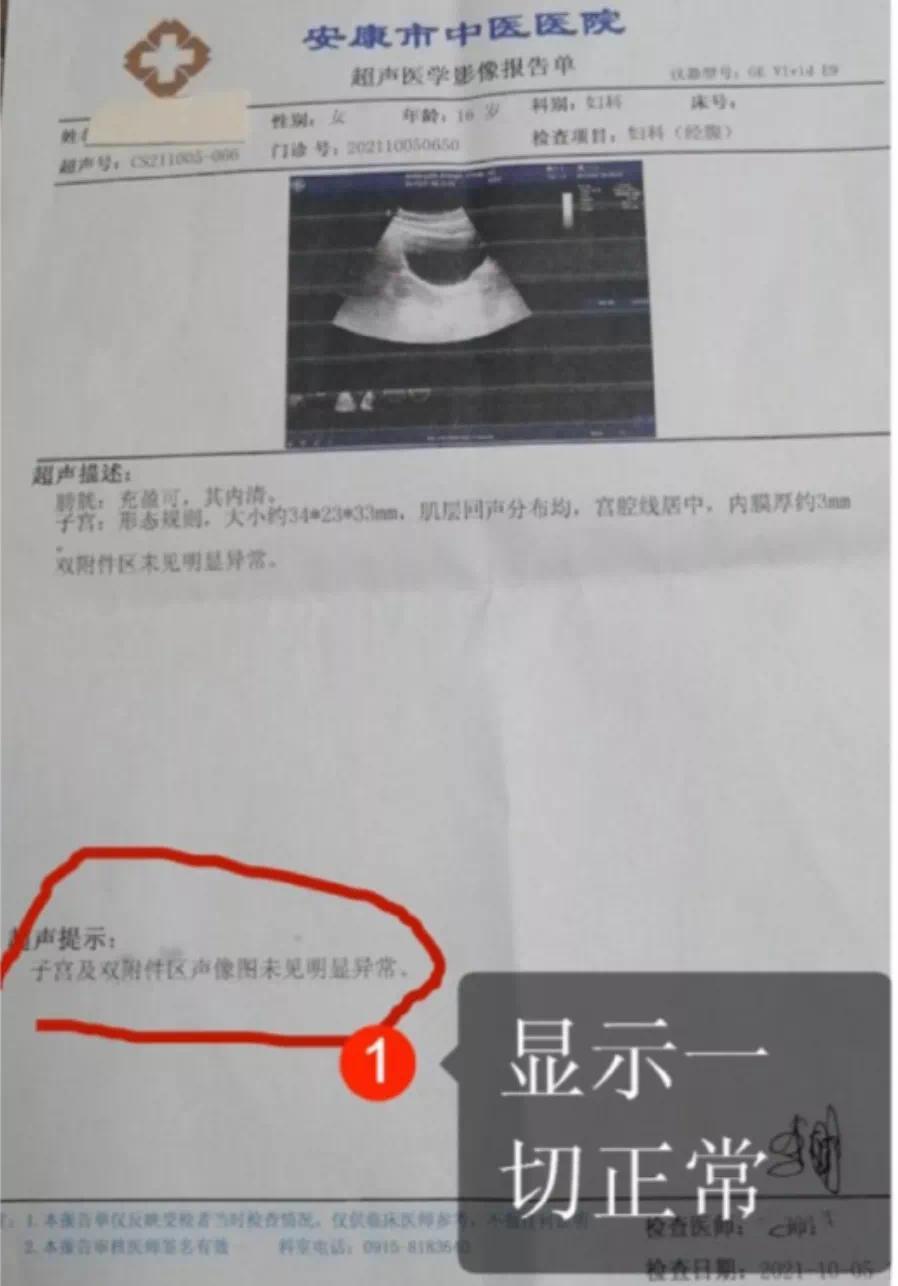

无病女学生被推上手术台当地最新通报

图片尺寸898x1286